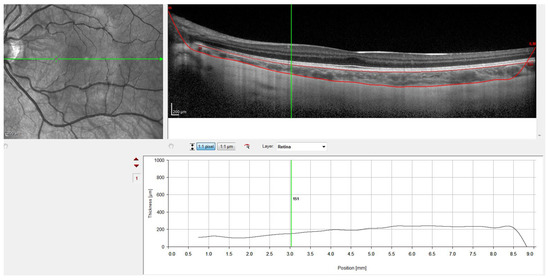

- Rahman, W.; Chen, F.K.; Yeoh, J.; Patel, P.; Tufail, A.; Da Cruz, L. Repeatability of Manual Subfoveal Choroidal Thickness Measurements in Healthy Subjects Using the Technique of Enhanced Depth Imaging Optical Coherence Tomography. Investig. Ophthalmol. Vis. Sci. 2011, 52, 2267–2271. [Google Scholar] [CrossRef]

- Spaide, R.F.; Koizumi, H.; Pozonni, M.C. Enhanced Depth Imaging Spectral-Domain Optical Coherence Tomography. Am. J. Ophthalmol. 2008, 146, 496–500. [Google Scholar] [CrossRef] [PubMed]